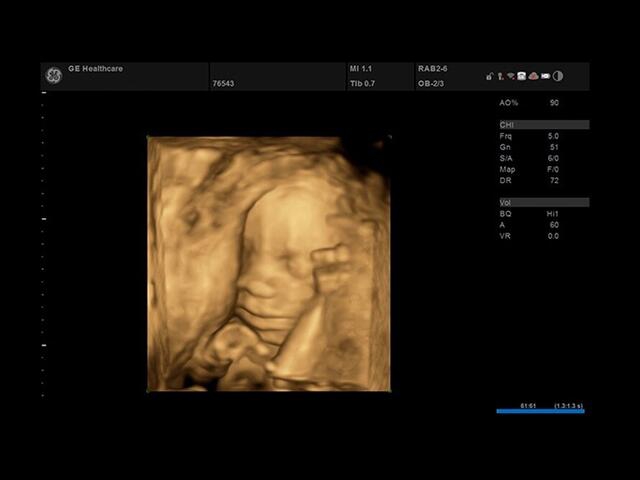

УЗИ-аппарат

GE Versana Essential

Ультразвуковой сканер GE Versana Essential отличается высокой точностью и мобильностью. Он широко используется при обследовании скелетно-мышечной системы и является незаменимым инструментом в урологии, гинекологии, педиатрии и общей радиологии.

Благодаря передовым технологиям и инновационным функциям, ультразвуковой сканер GE Versana Essential обеспечивает высокую четкость и детализацию получаемых изображений. Он позволяет врачам проводить диагностику и оценку состояния тканей и органов с высокой точностью, что способствует более точным и эффективным клиническим решениям.

• SonoBiometry : Эта функция позволяет быстро измерить биометрические параметры плода, такие как длина бедра, окружность головы, окружность живота и длина кости. Это важно для контроля развития плода и оценки его состояния.

• VOCAL : Это 3D-инструмент, который позволяет рассчитывать объем участков эксцентрической формы или сложных анатомических структур. Он полезен при анализе и измерении объемных образований внутри органов.